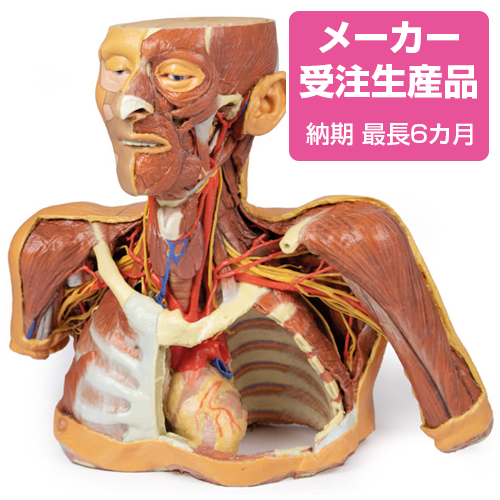

脳動脈 血管造影 : 正常解剖学 | e-Anatomy, NEW!頭部から胸部の解剖 | 京都科学,

NEW!頭部から胸部の解剖 | 京都科学, CT・MRI画像解剖ポケットアトラス 第4版 2巻 胸部・心臓・腹部,